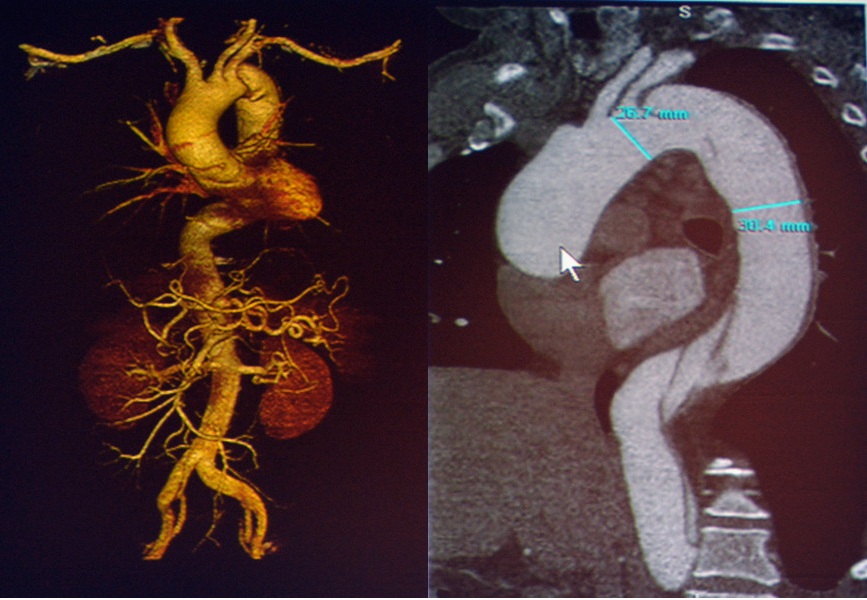

胸痛三联扫描(TRO)即一次CT扫描同时获得冠状动脉、肺动脉和主动脉的相关信息;64排128层螺旋CT即可完成TRO,一次注药、一次扫描就能清晰显示肺动脉主干段及亚段以上分支、左右冠状动脉主干及主要分支、胸主动脉以及胸部组织结构,同时将扫描所得图像经过强大的工作站后处理进行不同的图像重建和数据分析,可以得到多种三维重建图像,提供多项诊断信息。TRO可迅速准确地鉴别ACS、肺栓塞、主动脉夹层等急性胸痛的诊断,同时还可以帮助鉴别其他原因的胸痛。

图10-11 壁间血肿

图12 穿透性溃疡